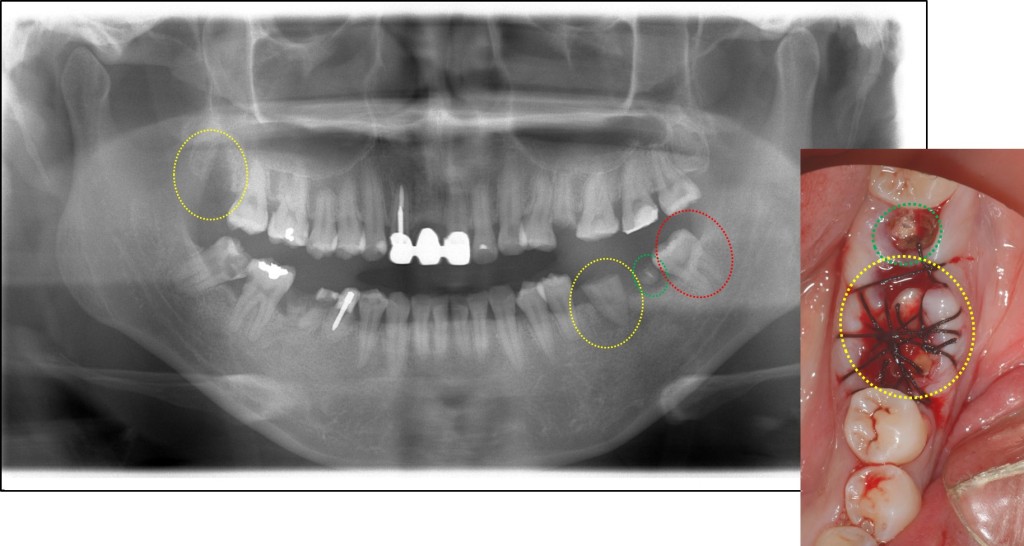

下写真をご覧ください。

黄色〇(親知らず)を移植したレントゲン写真と移植後に縫合した口腔内写真になります。緑〇の歯は後日抜歯しました。